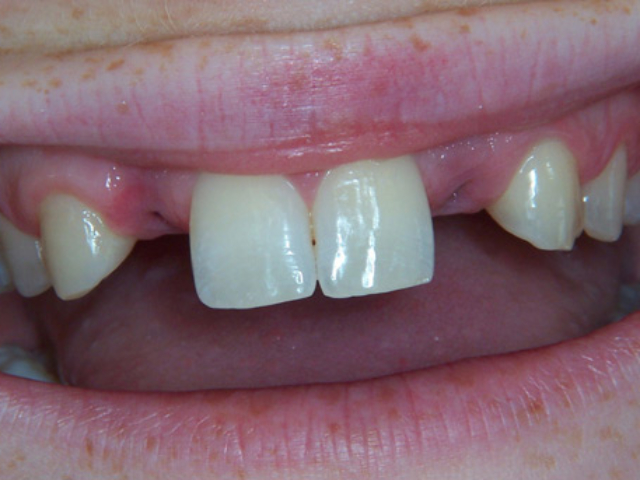

Case Study 8

Problem: This young patient was born with no lateral incisors.

Plan: Our plan… placed patient in orthodontics to straighten and gain the needed space then placed implants with crowns.

Treating genetic conditions.